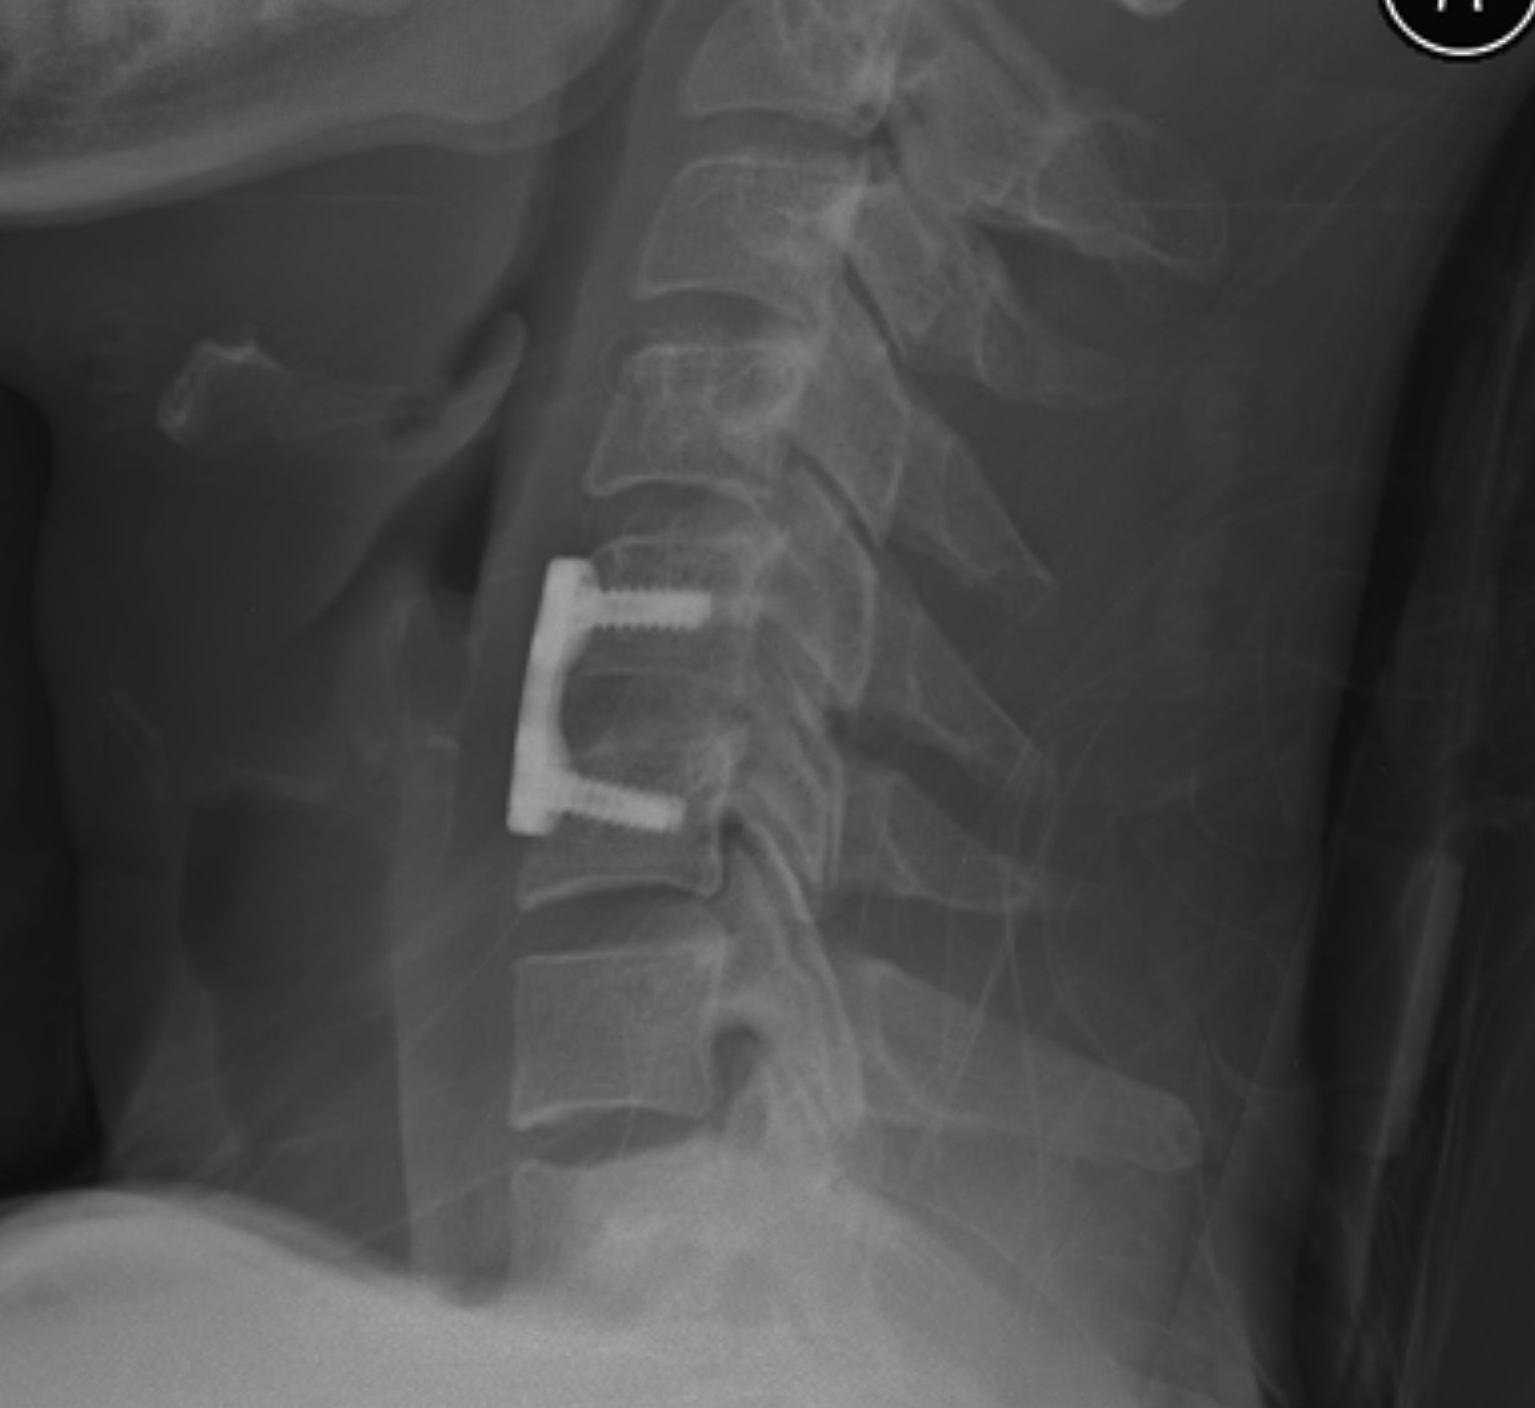

Anterior approach and ACDF

Advantage

- lower infection rates

- simpler patient positioning in multi-trauma patient

- can perform discectomy prior to reduction

Disadvantage

- ? more difficult to perform open reduction

- ? stable enough fixation given damage to posterior ligamentous structures

Technique

- decompression / discectomy

- reduction manoeuvre if needed using pins in vertebral bodies

- bone graft and plate